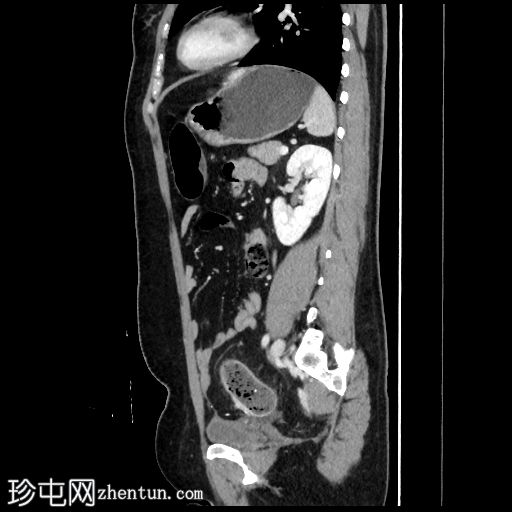

矢状位增强扫描(门静脉期)

线状包膜和实质钙化,呈“龟背样”外观

降结肠壁增厚(壁厚达7毫米),15厘米

段,直血管明显,伴脂肪浸润

乙状结肠和降结肠壁钙化

组织病理学报告确诊为血吸虫病背景下的侵袭性乙状结肠腺癌。